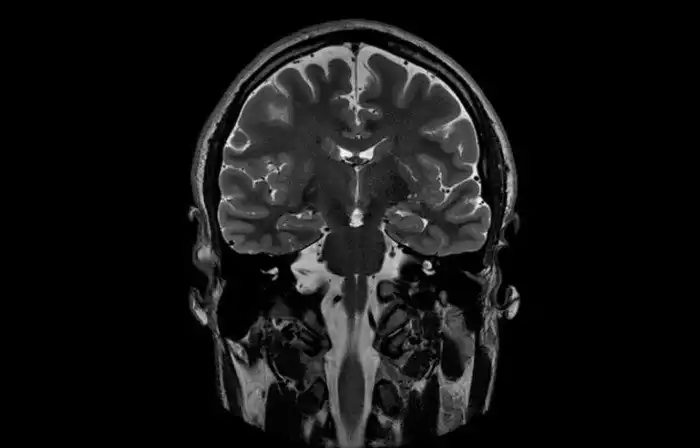

Слепота и диссоциативное расстройство личности

33-летняя пациентка психотерапевтической клиники в Германии ослепла в 13 лет. Женщина страдала от диссоциативного расстройства личности — в ней уживалось свыше 10 личностей. Примечательно, что спустя 20 лет некоторые из её личностей стали снова видеть. Слепыми остались только две личности. Энцифалограма мозга показала, что пациентка не лжёт: если текущая личность была слепа, то мозг не демонстрировал электрическую активность на визуальные стимулы, и наоборот.